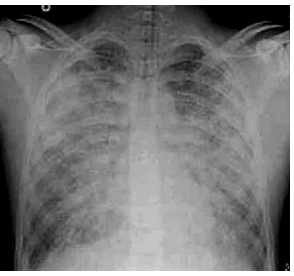

Você é chamado para discutir o caso de um paciente internado na UTI há 3 dias, com diagnóstico de síndrome do desconforto respiratório agudo (SDRA), em ventilação mecânica de difícil manejo. Histórico: Paciente masculino, de 27 anos de idade, hipertenso e dislipidêmico, busca atendimento hospitalar devido a febre, tosse e dispneia há 3 dias. Na admissão, apresentava-se com sinais de choque séptico e franca insuficiência respiratória. Na ausculta pulmonar, estertores creptantes presentes difusamente. O paciente foi encaminhado à UTI e submetido à ventilação mecânica, além de suporte clínico e prescrição farmacológica.

Parâmetros da ventilação mecânica atual: modo: ventilação assistida controlada; ciclagem: volume controlada; volume corrente: 6 mL/Kg; PEEP: 12 cm H2 O; FiO2 : 70%; FR: 30 ipm;relação. Inspiração: expiração: 1:1; pressão de Platô: 30 cm H2 O. Última gasometria: pH 7,22; PaO2 62 mmHg; PaCO2 69 mmHg; BE: –1,4 mmol/L; SaO2 86%; bicarbonato 20 mEq/L.

Exame de imagem:

(Disponível em: https://resources.wfsahq.org/ atotw/sindrome-do-desconforto-respiratorio-agudo/)